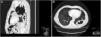

The chest radiography showed signs of pneumopericardium (Figure 1, long yellow arrows) and left cavitary lung mass. For better characterization, the patient underwent a computed tomography lung scan which revealed the extension (from the apex to the diaphragmatic surface) of the thick-walled gas-filled mass (Figure 2A/B, short black arrow) with an air-fluid level (Figure 2B, long black arrow) and distension of pericardial cavity with air-fluid level (Figure 2A/B, long yellow arrow) due to a direct pleuro-pericardial communication.